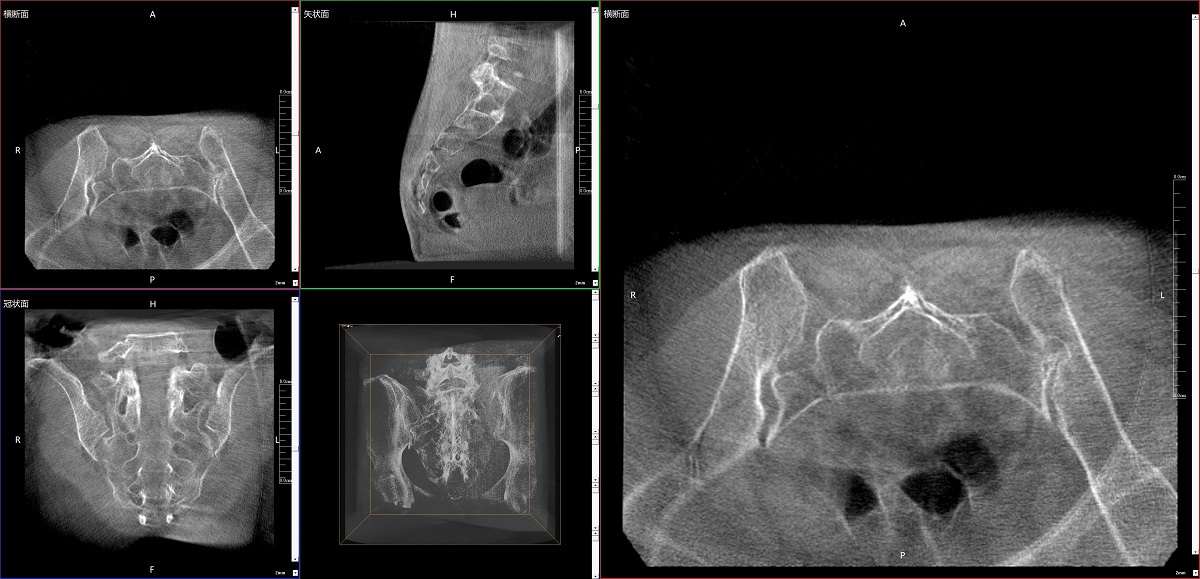

三維C形臂:精準(zhǔn)創(chuàng)傷手術(shù)的“導(dǎo)航之眼”

在骨科手術(shù)中,影像相當(dāng)于醫(yī)生的“眼睛”,要先“看得清",才能“算得準(zhǔn)” “打得穩(wěn)”。普愛醫(yī)療第三代平板三維C形臂協(xié)同醫(yī)院創(chuàng)傷導(dǎo)航機(jī)器人已開展多例“骨盆骨折微創(chuàng)手術(shù)”,成為上海市第七人民醫(yī)院手術(shù)技術(shù)創(chuàng)新的一大亮點(diǎn)。

普愛醫(yī)療第三代平板三維C形臂出色的二維透視和術(shù)中三維成像效果,為機(jī)器人提供了精確的術(shù)中影像依據(jù),協(xié)同提升手術(shù)整體的精準(zhǔn)度和效率,為患者帶來了更安全、更高效的醫(yī)療服務(wù)體驗(yàn)。